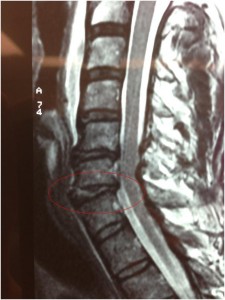

His presenting neurology was of elbow extension weakness of the right arm in the setting of severe neck and arm pain. Pre-operative MRI (see image above) showed evidence of disc disruption at the C5/6 and C6/7 levels with considerable nerve root compromise at each of these levels.